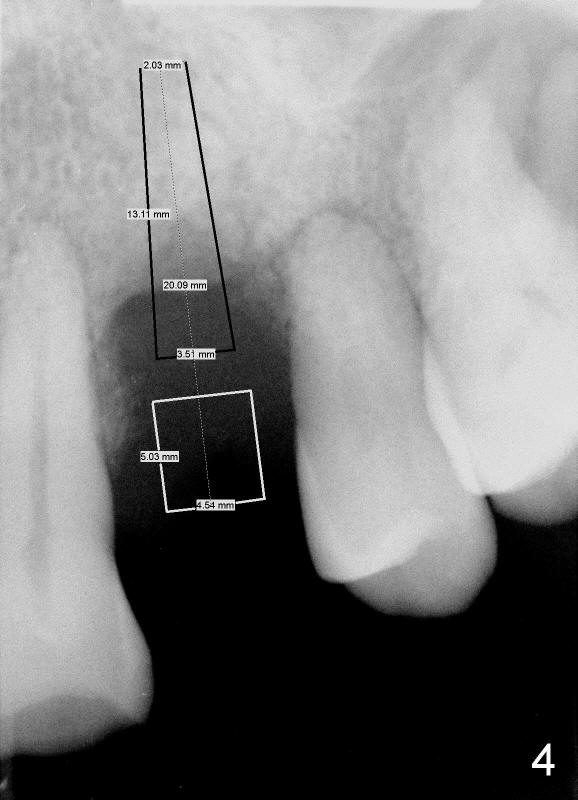

Dear Dr. Borgner: This Friday I may try D implant in a 50-year-old perio patient in #12 (Fig.1 *, Fig.2 is magnification of Fig.1 with sinus floor pointed by arrowheads), which was extracted ~ 1 month ago. PAs were taken yesterday (Fig.3). The socket must be partially empty. Can we start with RT2 or D1 spreader before using D2 one? #15 appears to be unnecessary. Tuesday, June 25, 2013 6:40 AM

Dr Wei, This is exactly what we spoke about in the class. 1- You can go right to the D2 channel former turned 90 degrees (Fig.4: design of D2 implant turned 90 degree). 2- Engage all of the apical bone you can without entering the sinus. 3- Do not remove any bone with a bur in order to not remove any remaining interseptal bone ! 4- Place a D2 implant as directed previously. This should work perfectly if you follow these steps. Dr Borgner Thursday, June 27, 2013 2:32 PM